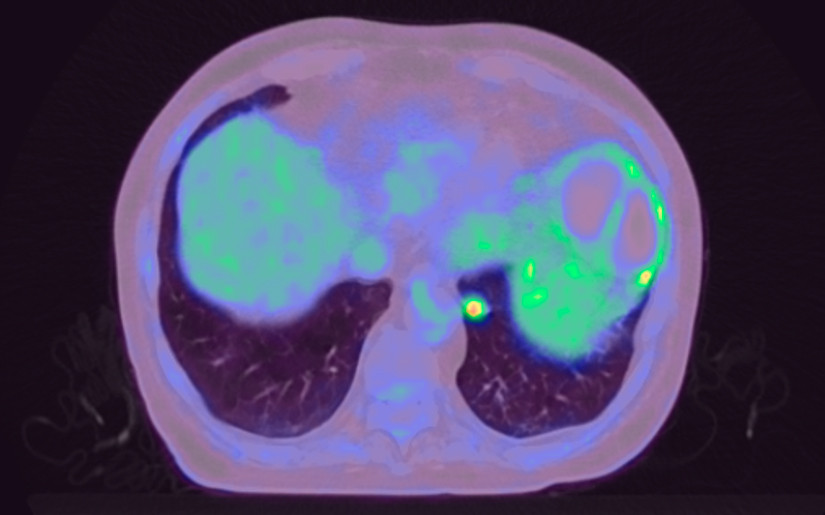

Pasienten utviklet i mellomtiden magesmerter og utspilt buk. Grunnet respirasjonsbesvær ble han lagt på intensivpost med respirasjonsstøtte. Endoskopisk ultralydundersøkelse måtte utsettes, men man gjorde ny FDG-PET/CT fire år etter siste undersøkelse. Denne gangen var det økt FDG-opptak basalt i venstre underlappstumor (figur 3).

De to første FDG-PET/CT-undersøkelsene kunne imidlertid gi grunn til mistanke om både falskt positive og falskt negative funn, da første undersøkelse ble tatt for tidlig etter prøvetaking av tumor og andre med forhøyet blodsukker. Oktreotidscintigrafi kan også underestimere opptak for nevroendokrine tumorer under 2 cm. Vi burde derfor lagt mer vekt på å få avklart lungeforandringen tidligere i forløpet, helst med perkutan lungebiopsi etter at den første finnålsaspirasjonscytologien fra lungetumor ikke ga konklusiv diagnose. Ved klinisk funn av hyperkortisolisme kan ikke én enkelt negativ cytologisk prøvetaking tillegges avgjørende vekt.

Ved symptomresidiv medførte interkurrent sykdom samt oppfølging av andre funn at ny prøvetaking stadig ble utsatt. I dag er PET/CT med 68Ga-DOTATOC et alternativ i utredningen. Denne er mer følsom for nevroendokrine tumorer med lav Ki67 enn FDG-PET/CT (5) (ramme 2).